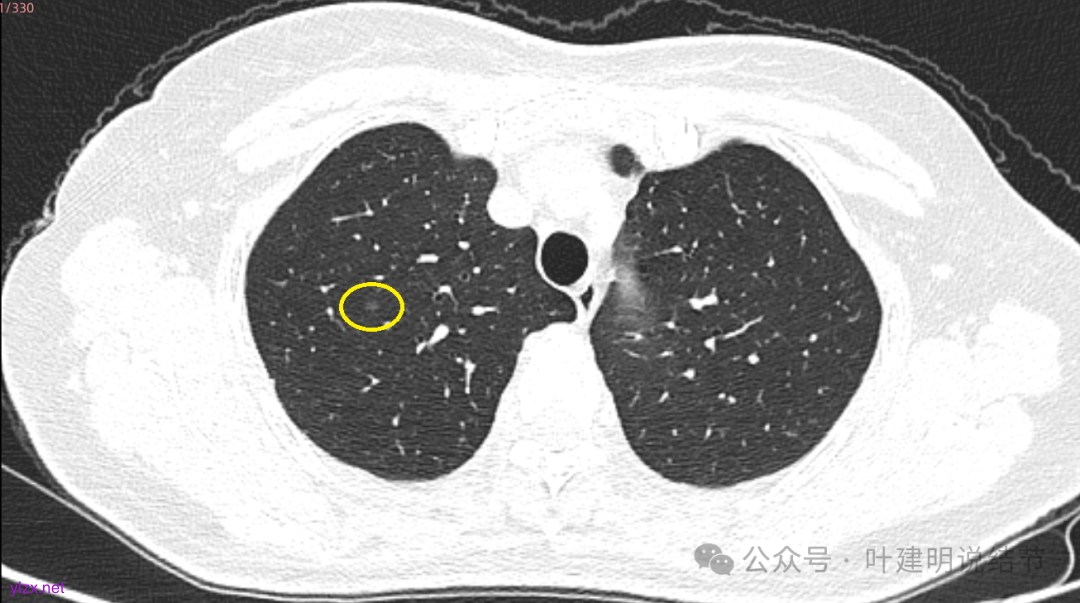

先来看2025年3月的影像:

两肺多发磨玻璃结节,我们主要看最主要的病灶有没有风险或者有没有进展就可以。我是先看2025年的,黄色的微小磨玻璃结节,密度很低,但是轮廓较为清楚,需要考虑肺泡上皮增生或者肺泡间隔增宽,严格意义上应该没有算肺癌,但是以后有可能会发展到不典型增生或者原位癌,当然也可能永远发展不到那个程度,所以目前不需要管;蓝色的到底是肺泡上皮增生还是少许慢性炎不太好确定,因为轮廓稍显模糊,但它又是磨玻璃密度,总归近期是能够随访的;橘色的密度比黄色的略高,有可能会使肺泡上皮增生或者不典型增生,目前也仍可以随访;粉色的是主病灶,位于左肺上叶,混合密度,表面毛糙,由小血管进入,单次看需要考虑微浸润性腺癌可能性较大。然后我们再来看2020年的影像,因为除了粉色的其他的都没有风险,所以不需要一一去找出来,重点关注粉色这处当时是怎样的。我们发现这个病灶5年前就有,也有小血管进入,也有表面毛糙,也是磨玻璃密度,但是当时磨玻璃当中没有实性的成分,是纯磨玻璃伴微小血管进入。对比起来看,这个病灶在5年当中略有进展,原来应该是腺体前驱病变,现在应该是原位癌或者微浸润性腺癌。那么是不是现在就到了一定得马上手术的程度呢?这个仍然可能是不同医生意见会有出入的。假如说从再随访是不是马上会转移来讲,这么小的肿瘤,发展这么慢,而且仍然含有磨玻璃成分,病理考虑与微浸润性腺癌可能性较大,应该仍然不至于说没有随访的空间。但是如果继续随反思想压力比较大,以及即便在随访后续仍然总得要开刀来说,加上病灶位置靠胸膜并不远,简单的单孔胸腔镜楔形切除就能解决问题,将有一定风险的这个病灶切了,同样是可行的。这需要你自己权衡决定。我没有办法100%给十分确切的意见。但是如果从倾向性来讲,由于是多发病灶,加上年纪还轻,风险还不是很大,稍微清一下雨6~9个月复查,有进展病风险再增加再考虑手术。意见供你参考!